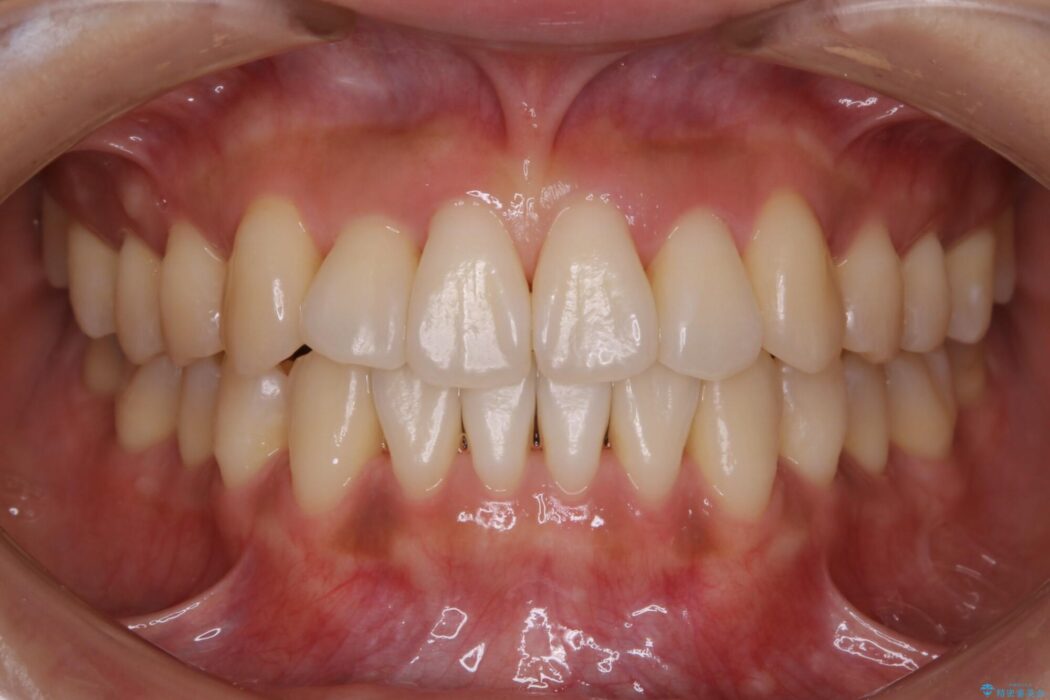

前歯のガタガタを気にされて来院されました。

検査の結果、骨の厚みに余裕がないことが判明しましたので、幅の拡大と歯の側面を削るIPRでは歯周病に対する不安を拭いきれないと判断しました。

よってマイクロインプラントを用い、奥歯から順番に遠心移動させることによってスペースを確保することにしました。